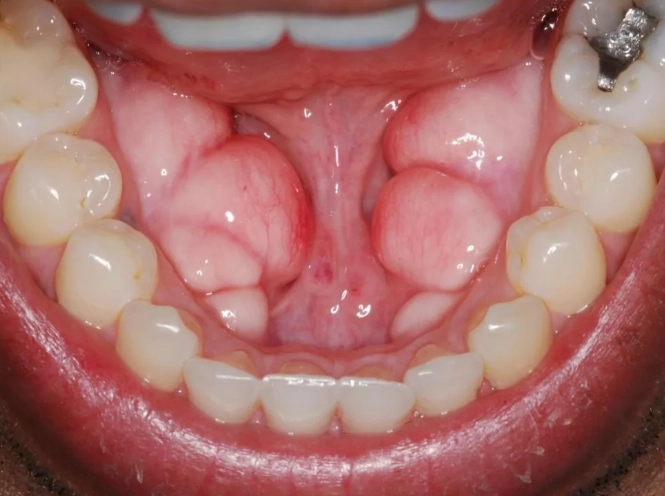

| Torus Mandibularis | On the inner surface of the lower jaw (mandible), near the premolars. | Usually bilateral (on both sides). Often round or spindle-shaped bumps. | More common in men. Affects about 6-12% of people. |

The first time a patient feels one, they often panic. I remember a young man, let's call him David, who was convinced he had oral cancer because he found bilateral lumps under his tongue. A quick examination confirmed they were classic, symmetrical mandibular tori. He'd had them for years but only just noticed. That's the other thing—they grow so slowly you often don't realize they're there.